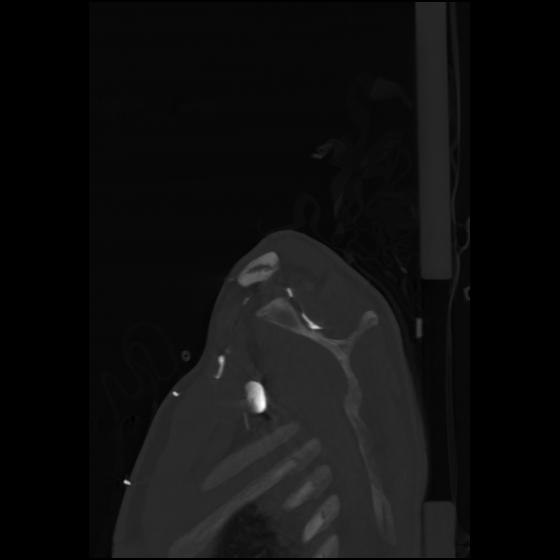

24 ANGIO,CE,Sag-MIP,5.000,ANGIO,Sag-MIP,